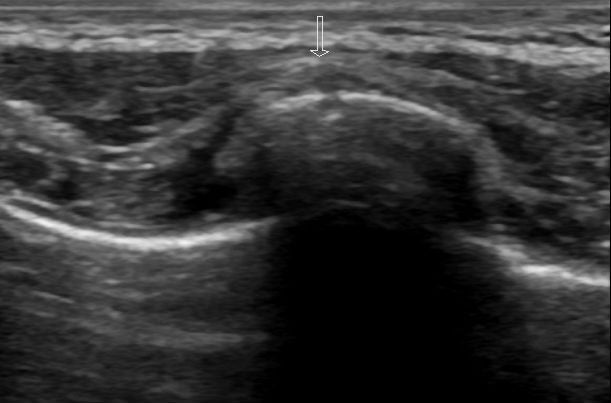

Figure 4:

Transverse view again demonstrating a cortical break with overlying hematoma.

The example images and annotations are courtesy of Dr. Maulik S Patel, Radiopaedia.org. From the case rID: 16479